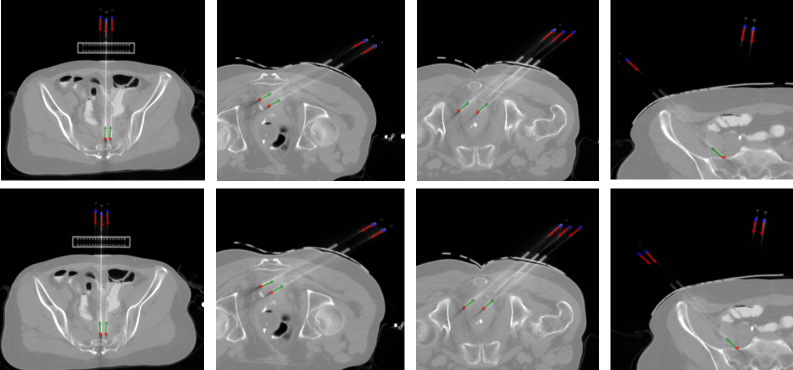

From Fig. 4, it can be observed that the detection network accurately identifies the positions and orientations of both the needle tips and handles. The predicted results (bottom row) closely align with the ground truth annotations (top row), demonstrating the network’s reliability in localizing and orienting the needles across different CT slices. Notably, in the last column, the network successfully detects a faint needle handle that was not annotated in the ground truth due to its subtle appearance, highlighting its sensitivity to challenging cases that are difficult to observe.